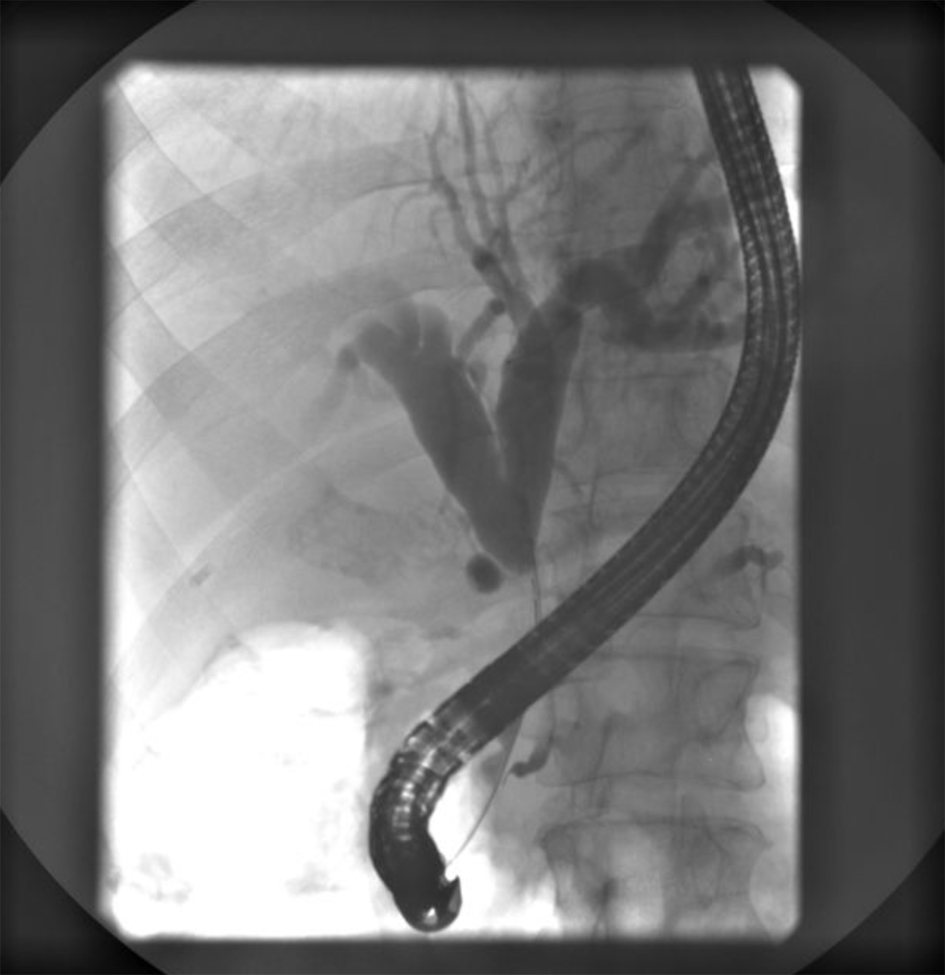

Endoscopic retrograde ERCP was made and showed a stenosis of common bile duct 3 cm in length with prestenotic dilatation of both left and right hepatic duct and intrahepatic bile ducts (Fig. 4). A papilotomy was then made, brush aspiration for cytological analysis and a biliary plastic stent (Amsterdam 10F, 6 cm) was inserted at the site of stenosis with good bile drainage (Fig. 5).

![]() Click for large image | Figure 4. ERCP showing a subtotal stenosis of the common bile duct 3 cm in length with expressed prestenotic dilatation of both hepatic ducts and intrahepatic bile ducts. |